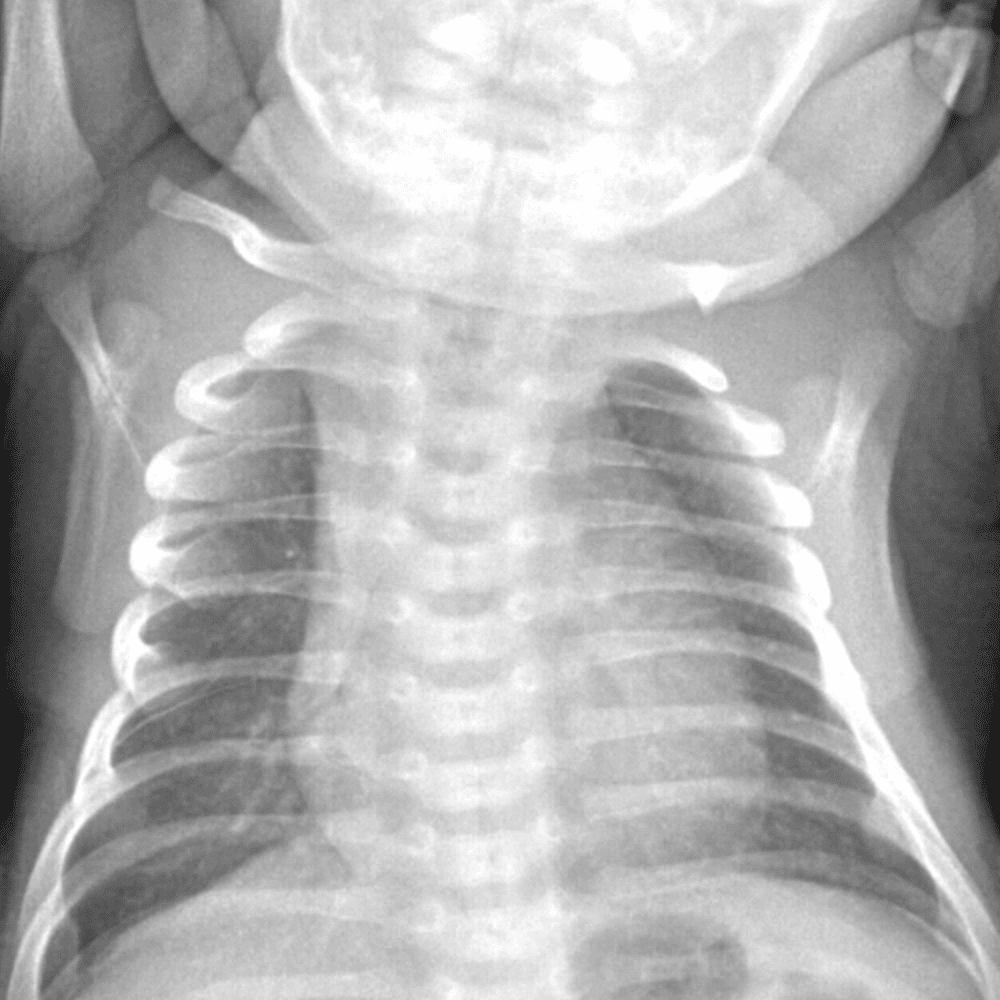

Peds Chest

Practice

Simulates call by including subtle or difficult cases and some normals.

50 cases